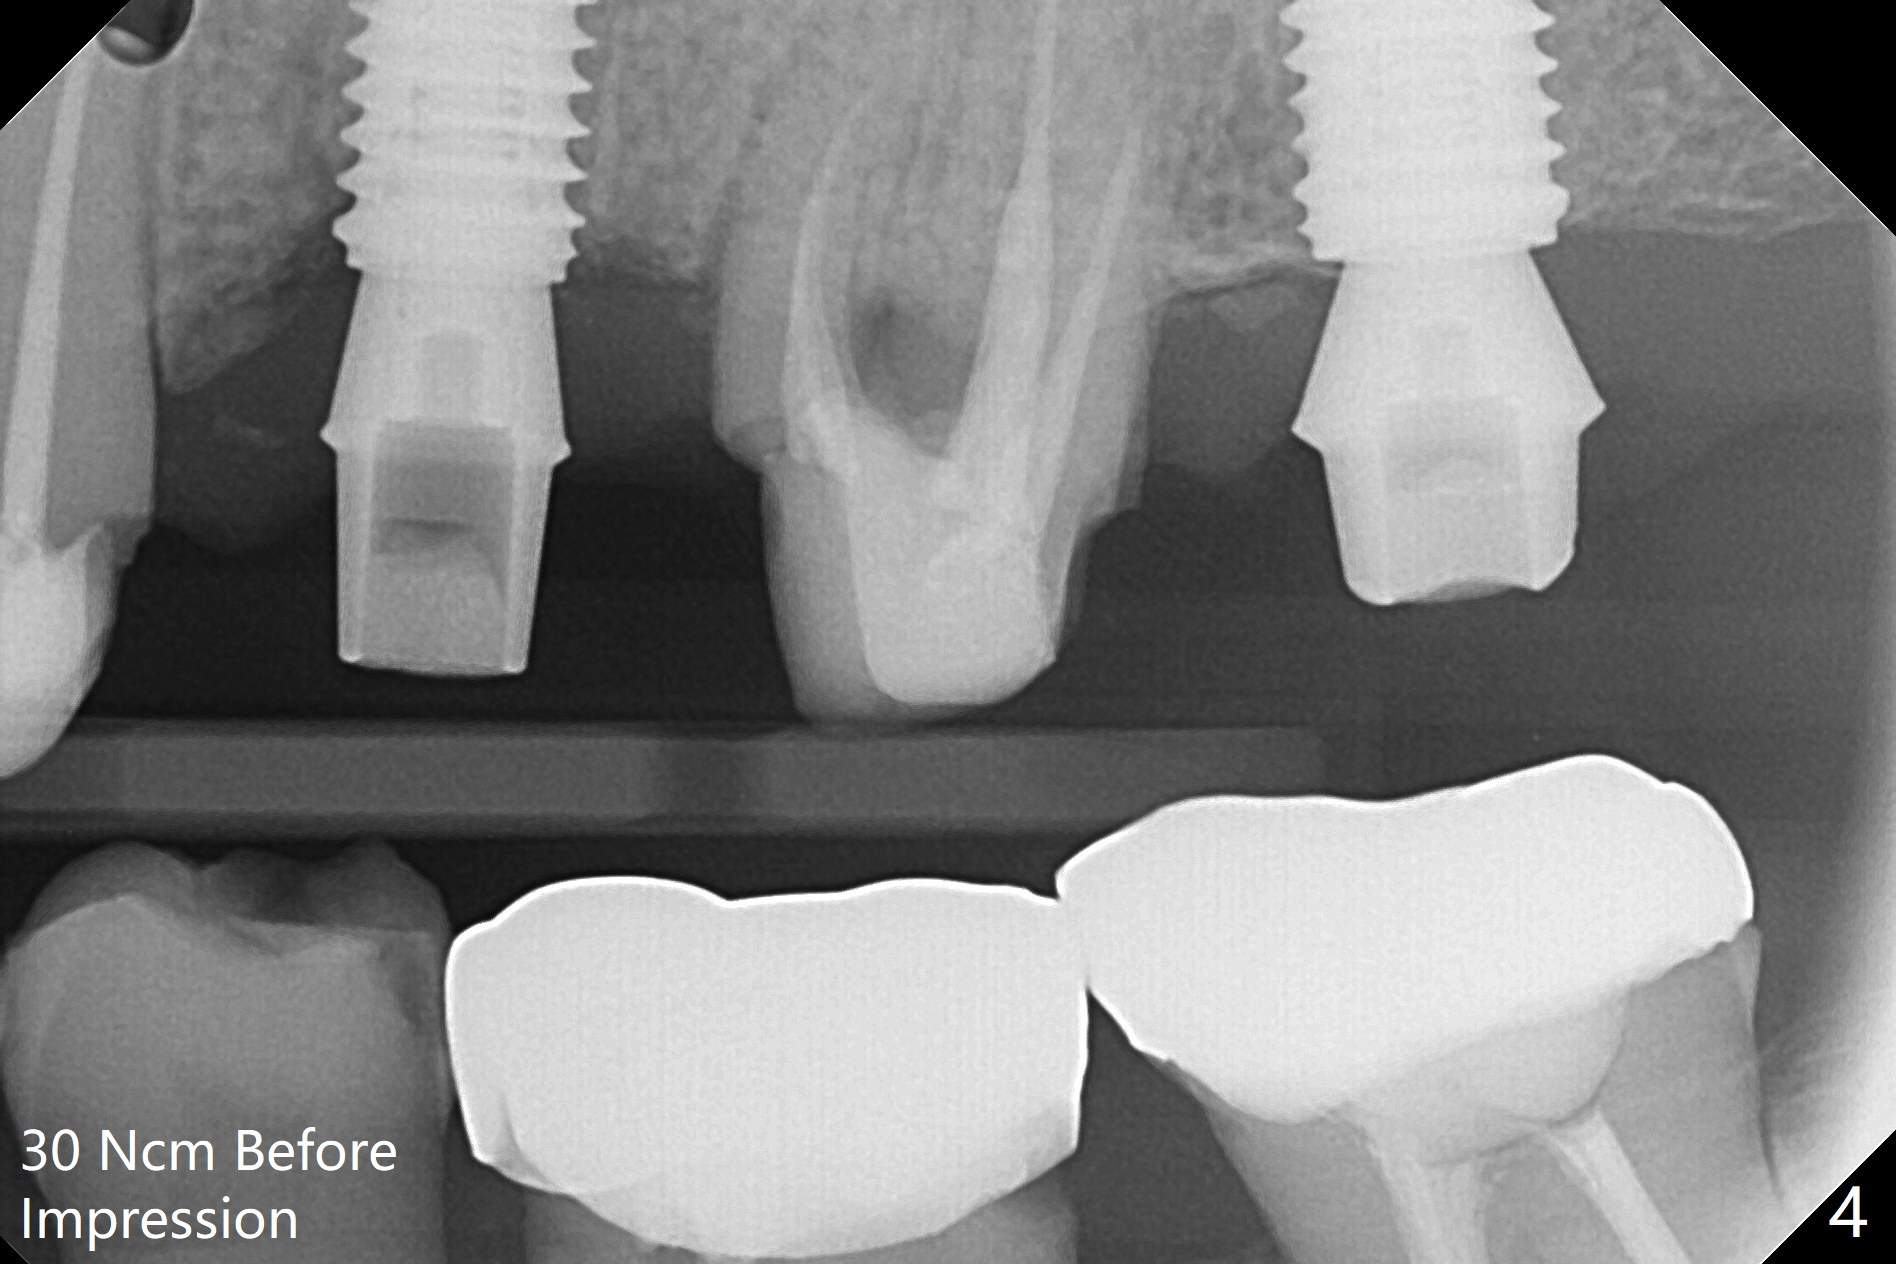

After underdrilling (3.5x14.5 mm drill (10.5 mm offset), a 4.5x11.5 mm implant is unable to enter the osteotomy at #13; following use of 4x10 mm drill (partial normal drilling), the implant is inserted smoothly with insertion torque ~ 35 Ncm. Sticky bone is placed in the bony portion of the buccal gap, while 2 pieces of PRF membrane in the gingival portion of the buccal gap. The bone density at #15 is low, the insertion torque is ~15 Ncm with normal drilling without cortical tap (Fig.1). The procedure is smooth in part due to no sinus involvement (red dashed line). An immediate provisional FPD is fabricated for #12-14. But local oral hygiene is difficult to maintenance. When the wound heals at #13, the FPD is removed. The bone loss is minimal nearly 4 months postop; the abutment at #13 is incompletely seated (Fig.2 arrowheads: gap). After repositioning, the abutment is re-seated completely without gap (arrowheads); a 5.7x4(3) mm cemented abutment is placed at #15 (Fig.3,4). Four crowns are cemented 4 months 10 days postop (Fig.5).